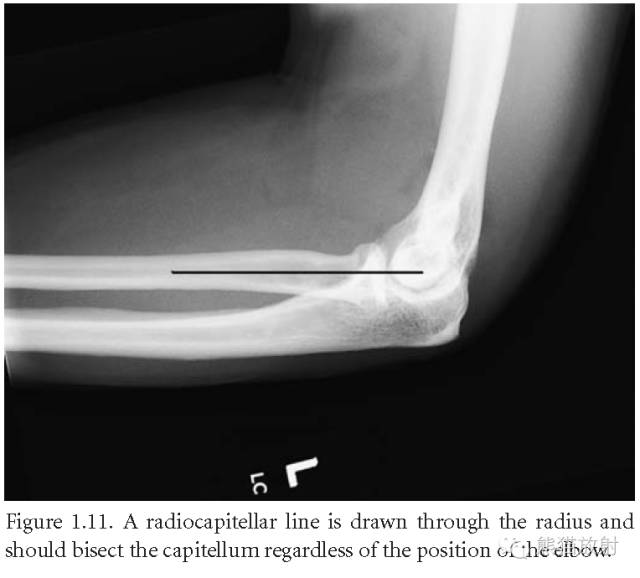

桡肱小头线:沿桡骨干近段画线,在任何投照位上,其平分肱骨小头。